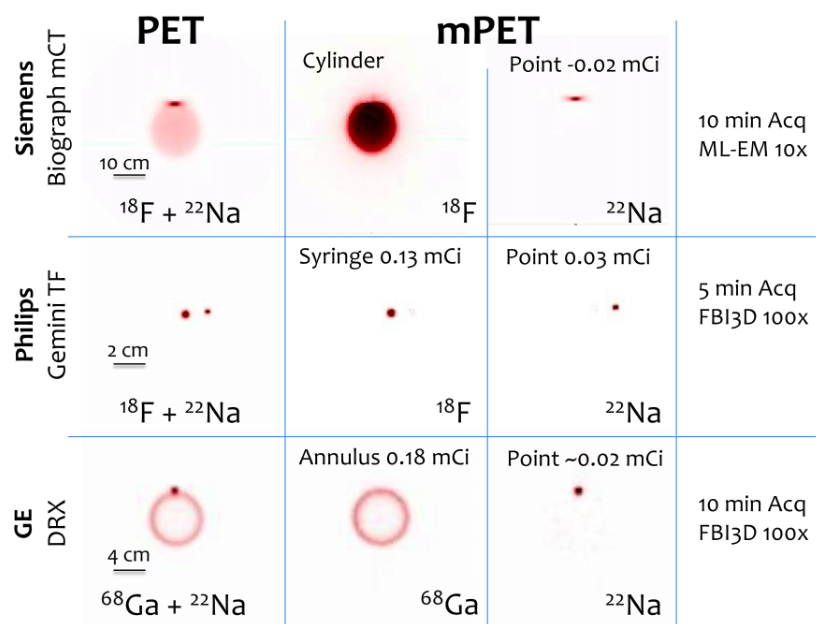

| ABSTRACT | Introduction: Simultaneous in-vivo imaging of several biological processes may improve oncological, neurological and cardiovascular studies by providing complementary information obtained under the same exact conditions and coregistered in space and time. Standard PET imaging does not allow multiplexed acquisitions, as all annihilation photons have the same energy. We developed a technique called multiplexed PET (mPET), which uses a tracer labelled with a pure positron emitter (such as 18 F, 13 N, 11 C), and a tracer labeled with a positrongamma emitter (such as 124 I, 76 Br, 82 Rb, 86 Y). Positrongamma emitters generate a significant number of triplecoincidences , which allows them to be differentiated from the standard PET radionuclides . In this work, we evaluated the performance of mPET using phantom and animal experiments. |

| JOURNAL | IEEE Nuclear Science Symposium & Medical Imaging Conference, 2014 |

| ABSTRACT | Simultaneous noninvasive evaluation of biological processes can improve molecular imaging by providing complementary tissue functions under equivalent conditions coregistered in space and time. Positron Emission Tomography (PET) is the most sensitive noninvasive molecular imaging tool, able to measure many physiological properties with a number of radiotracers. Unfortunately, positron annihilation gamma rays are identical for all radiotracers, making them indistinguishable with standard PET imaging. This fact has motivated attempts at dual tracer imaging with standard PET to distinguish radiotracers using timebased differences. |

| ABSTRACT | Positron emission tomography (PET) is one of the most sensitive noninvasive molecular imaging tool, being its sensitivity several orders of magnitude higher than that typically obtained in single photon emission computed tomography (SPECT). However, PET lacks the ability of SPECT to multiplex signals from several tracers, which is very useful in many different studies such as cardiac imaging with 99mTcSestamibi and 201Tl. Recently, it has been shown that the use of tracers labelled with positrongamma emitter radionuclides like (124I, 86Y, 82Rb, 94mTc, 76Br) in combination with tracers labelled with standard positronemitter radionuclides like (18F, 11C, 13N) enables multiplexed PET (mPET). mPET uses the triple coincidences from the positrongamma emitters, together with the standard double coincidences to reconstruct separated images of each radionuclide’s activity distribution. We obtained encouraging results with mPET in some initial preclinical studies, but a detailed study of the quality and quantification properties of mPET images, and an evaluation of its performance in realistic clinical scenarios was still required. |

| ABSTRACT | Simultaneous invivo imaging of the biodistribution of two or more radiotracers of interest with Positron Emission Tomography (PET) could provide more comprehensive information about specific targets and physiological processes of interest; however, conventional PET cannot separate different positronemitting radionuclides based on the energy of the detected gamma photons. We have shown previously that the detection of triplecoincidence events allows the separation of radiotracers labeled with positron + gamma emitters (like 124 I) from others labeled with standard pure positron emitters (like 18 F), without requiring any kinetic modelling or precise energy measurement. The goal of the current study was to demonstrate that this methodology can also be applied to clinical PET scanners. |